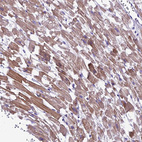

Immunohistochemical staining of human Smooth muscle shows to strong granular cytoplasmic positivity in smooth muscle cells.